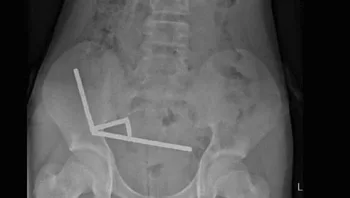

בלע צ'ופסטיק - וחי איתו תקוע בגרון במשך שמונה שנים